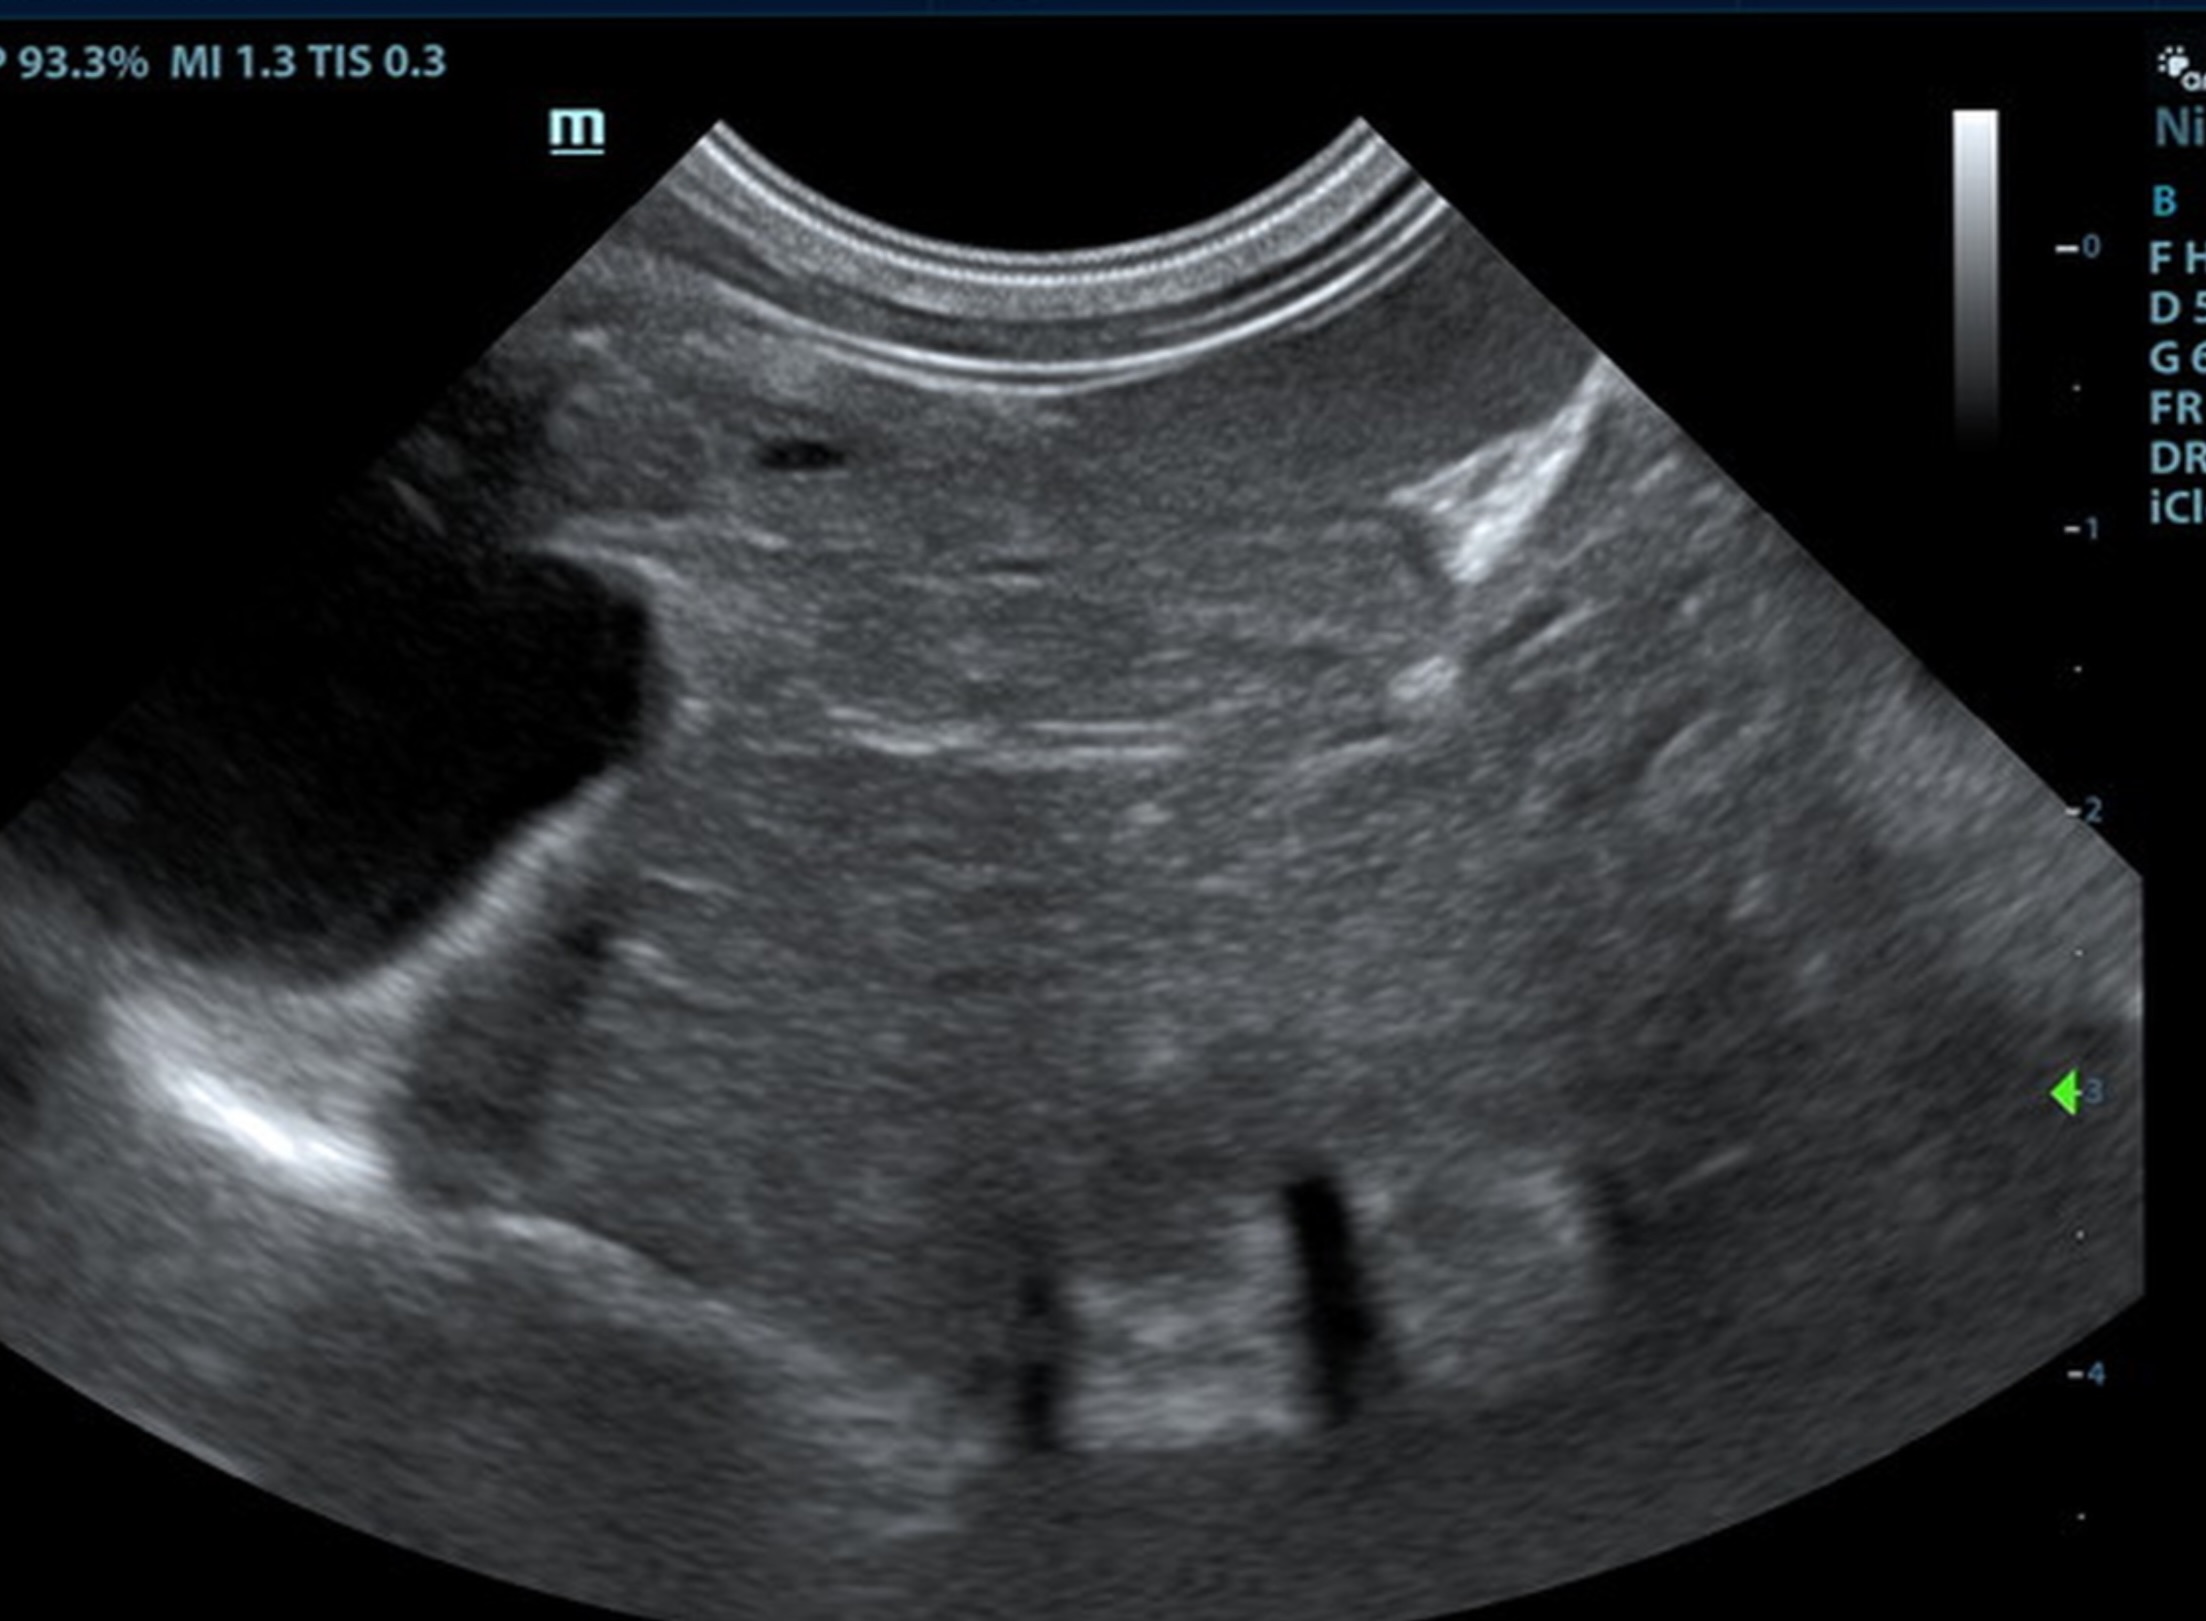

The liver was subnormal in size, yet the portal vein and vena cava ratio was 1:1. The portal veins were subnormal in size and measured 0.34 cm. The vena cava was enlarged and measured 0.34 cm. The vena cava was enlarged and measured 0.72 cm, aorta measured 0.4 cm. The branching of the portal vein appeared to be normal and of adequate volume. The portal vein and vena cava measured 0.5 cm each in the extrahepatic space. The splenic vein entry into the portal vein and gastroduodenal vein entry into the portal vein appear to be normal. There was one turbulent vessel in the region of the central branch of the portal vein, which may represent an intrahepatic shunt, but this could not be confirmed. The width of the shunt is approximately 0.76 cm. This is in position of central divisional shunt; however, right divisional origin cannot be completely ruled out. The gallbladder presented acceptably thin walls with primarily anechoic content. The cystic and common bile ducts were normal.